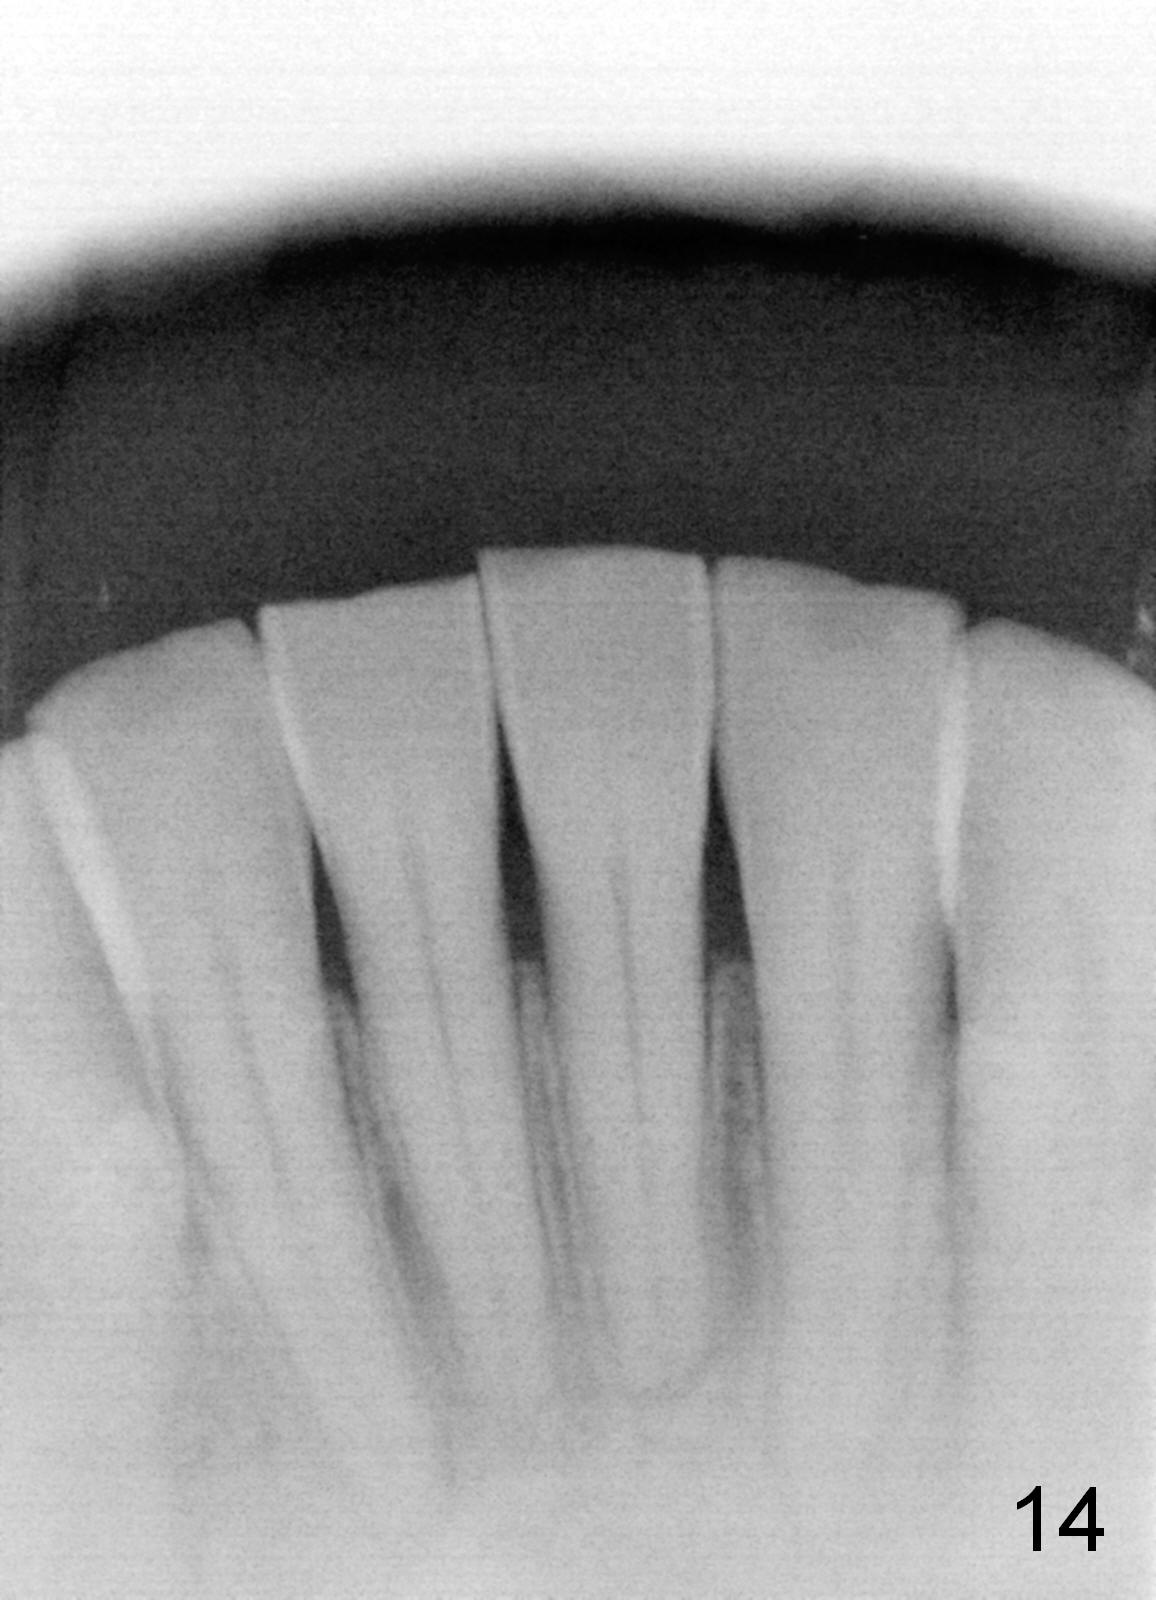

To correct the gingival margin associated with #8 implant, bone graft is needed.  Particulate graft may not stay in place. Chin graft is harvested.  Since the roots of the lower anterior teeth are long (Fig.8), the width of the chin graft is limited for direct screw fixation (Fig.9,10).  Titanium mesh is used for fixation of the graft.  Connective tissue graft from the palate is to increase bulk at the site of #8 (Fig.11 *).  There is no symptom or sign of infection 1 month postop (Fig.12,13).  Although there is alteration of sensation of the lower incisors, there is no apical radiolucency of them 4 months postop (Fig14).  There is no abnormality associated with the bone graft and Titanium mesh (Fig.15).